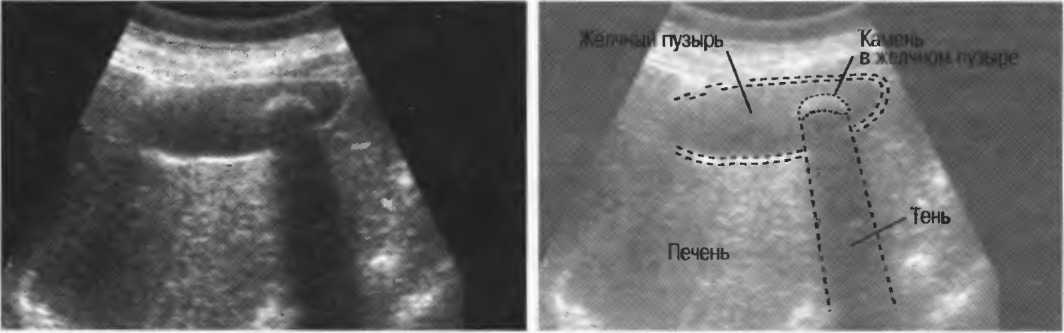

Рис. 17а. Большая акустическая тень за камнем в желчном пузыре.